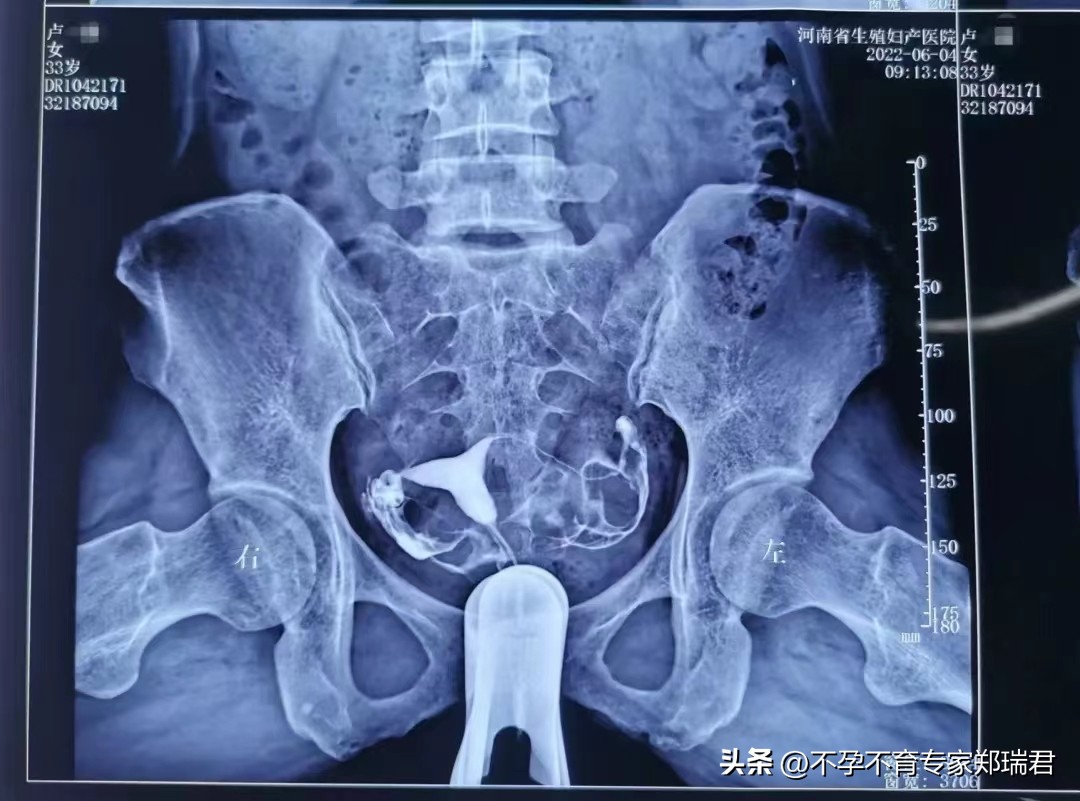

2022年6月4号复查子宫输卵管造影示:宫体右偏,双侧输卵管已通:

复查造影后治疗7天,7月经期治疗7天,诊断通液显示:输卵管稍有阻力,回流2.5ml,无回抽。

又巩固治疗,通液术后第2个经期治疗后试孕,试孕第1个经期怀孕。